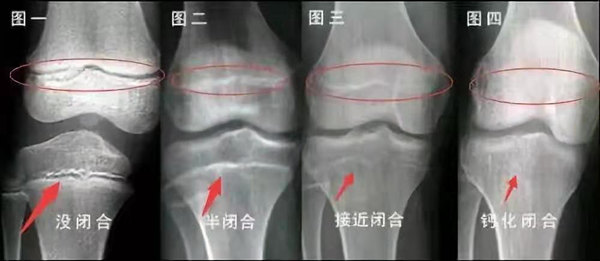

未成年時(shí)隨著年齡的增加骺軟骨端不斷骨化,骨骼就不斷增長(zhǎng)。當(dāng)骨骺線完全閉合時(shí)骨骼就停止生長(zhǎng),個(gè)子也就不再增長(zhǎng)了。一般骨骺端完全閉合的年齡是18~20歲左右。

青少年一般什么時(shí)候骨骺閉合?

一般女孩是在16歲,男孩是在18歲。

一般來(lái)說(shuō),女孩的骨齡超過14歲,男孩的骨齡超過16歲,這時(shí)其骨骺線已接近閉合,基本沒有長(zhǎng)高的機(jī)會(huì)了。

因此,越早了解骨骺線閉合情況,越早干預(yù),孩子長(zhǎng)高的可能性越大。